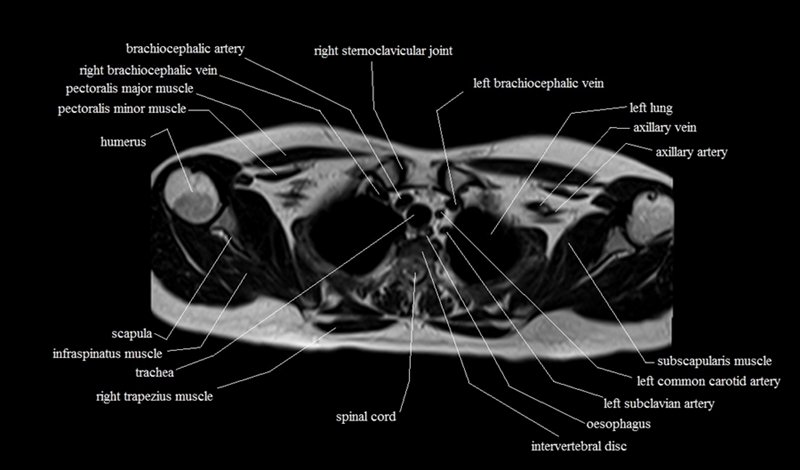

MRI Axial Cross Sectional Anatomy of Chest

This MRI chest (thorax) axial cross sectional anatomy tool is absolutely free to use. Use the mouse scroll wheel to move the images up and down, or alternatively, use the tiny arrows (→) on both sides of the image to navigate through the images. For a more detailed view, double-click the image to view it in full screen, and use the menu in the top right-hand corner to view individual slides or play them in a loop.